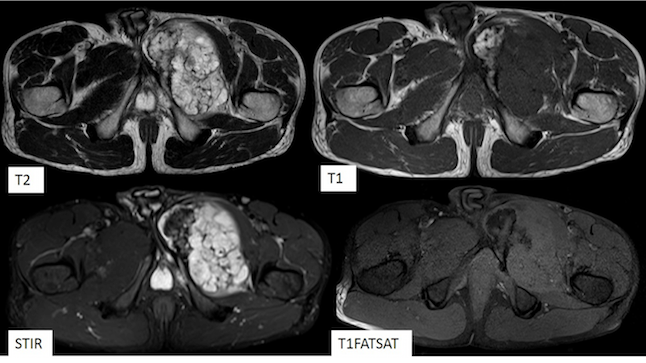

Figure 3. A large intramedullary mass lesion is noted arising from the body and near a portion of the left superior and inferior pubic rami. The lesion appears hyperintense on T2WI, STIR and hypointense on T1WI. The lesion has a short bony stalk with direct continuation with the underlying bone.

MRI with and without contrast

A large intramedullary mass lesion of 9.5x8x11 cm was noted arising from the body and near portion of left superior and inferior pubic rami. The lesion appears hyperintense on T2WI, STIR and hypointense on T1WI. The lesion has a short bony stalk with direct continuation with the underlying bone.

The bulk of the tumor is noted to protrude into the medial aspect of the left upper thigh, elevating the gracilis and adductor muscle with altered signal intensity (hyperintense on T2WI, STIR) within it. On post-contrast study, the lesion shows heterogeneous enhancement.